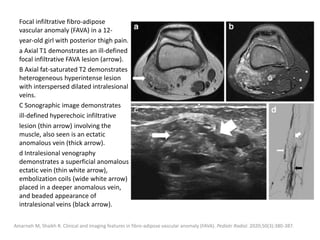

exclude underlying disorders.

Skin thickening is usually the only finding on US.

MRI findings are also subtle, with skin thickening

and occasional increased subcutaneous thickness

and faint focal T2 hyperintensity and contrast

enhancement.

Fayad LM, Hazirolan T, Bluemke D, Mitchell S. Vascular malformations in the extremities: emphasis on MR imaging features that guide

treatment options. Skeletal Radiol. 2006;35: 127-37.

Moukaddam H, Pollak J, Haims AH. MRI characteristics and classification of peripheral vascular malformations and tumors. Skeletal Radiol.

2009;38:535-47.